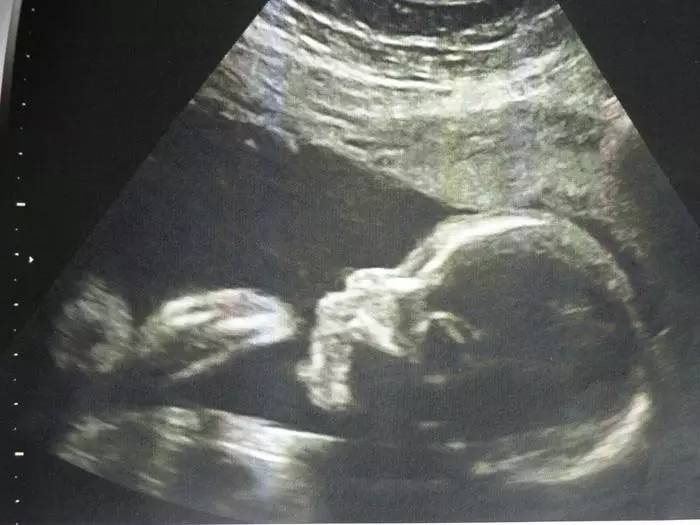

股骨(FL)

它的正常值与相应的怀孕月份的BPD相差2-3mm左右,一般在妊娠20周左右,通过测量FL来检查胎儿发育情况。